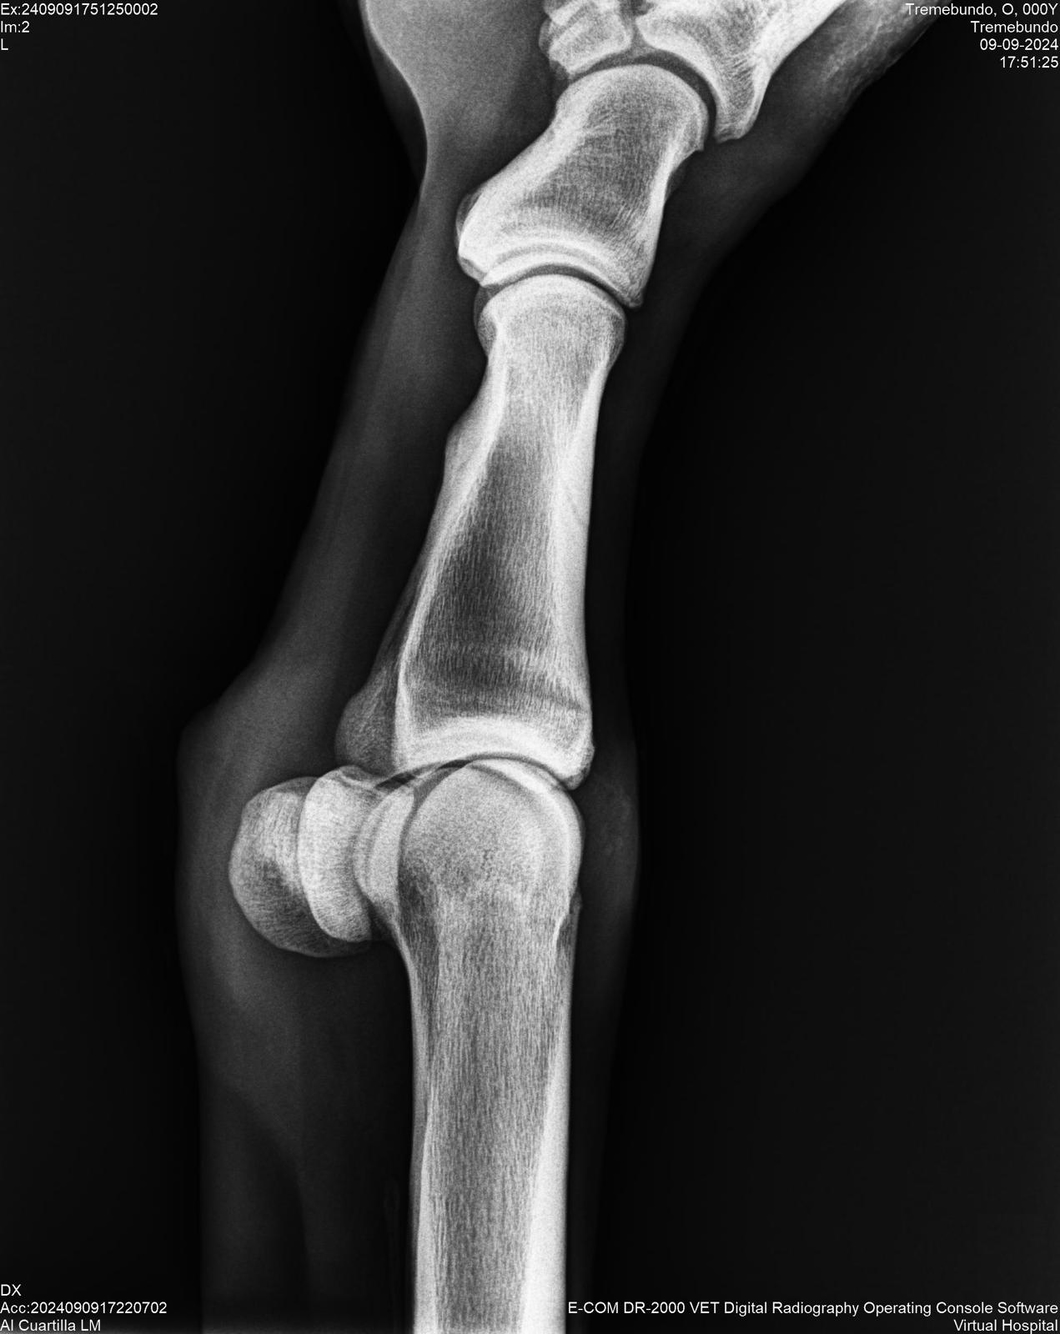

LOTE 37, TREMEBUNDO

Ficha del Lote

Identificador: #291140-

Generacion 2022